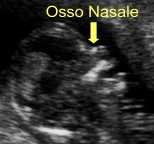

LEA, Livelli Essenziali di Assistenza, Curriculum Vitae, Padova, Vicenza, Venezia, Rovigo, Belluno, Verona, Treviso, Veneto, Harmony Test, ARIOSA, PrenatalSafe, Prenatal Safe, GENOMA, Vera Prenatal Test, Ecografia Tridimensionale, Ecografia Tridimensionale a Padova, Ecografia Tridimensionale a Vicenza, Test Combinato, Test Combinato a Padova, Test Combinato a Vicenza, Ultrascreen, Ultrascreen a Padova, Ultrascreen a Vicenza, Harmony Test, Harmony Test a Padova, Harmony Test a Vicenza, Ecografia 3D, Ecografia 3D a Padova, Ecografia 3D a Vicenza, Ecografia morfologica, Ecografia morfologica a Padova, Ecografia morfologica a Vicenza, Ecografia di I° livello, Ecografia di II° livello, Ecografia di 1° livello, Ecografia di 2° livello, Ecografia ostetrica, Ecografia ostetrica a Padova, Ecografia ostetrica a Vicenza, Ecografia in gravidanza, Ecografia in gravidanza a Padova, Bellitti Francesco Ginecologo, Ecografia in gravidanza a Vicenza, Ecografia 3 D, Ecografia 3 D a Padova, Ecografia 3 D a Vicenza, Ricerca DNA Fetale, Ricerca DNA Fetale a Padova, Ricerca DNA Fetale a Vicenza, Ecografia genetica, Ecografia genetica a Padova, Ecografia genetica Vicenza, Ecografista Accreditato, Ecografista Accreditato a Padova, Ecografista Accreditato a Vicenza, Ecografisti Accreditati, Ecografisti Accreditati a Padova, Ecografisti Accreditati a Vicenza, Bi-test, bi-test a Padova, bi-test a Vicenza, Osso nasale, osso nasale a Padova, osso nasale a Vicenza, Ostetricia, ostetricia Padova, ostetricia Vicenza, Ginecologia, ginecologia Padova, ginecologia Vicenza, Villocentesi, Villocentesi a Padova, Villocentesi a Vicenza, Amniocentesi, Amniocentesi a Padova, Amniocentesi a Vicenza, Ecografia ginecologica, Ecografia ginecologica a Padova, Ecografia ginecologica a Vicenza, Screening per la sindrome di Down, Screening per la sindrome di Down a Padova, Screening per la sindrome di Down a Vicenza, Test Harmony, Test Harmony a Padova, Test Harmony a Vicenza, Bitest, bitest a padova, bitest a Vicenza, Bi test, bi test a padova, bi test a Vicenza, 3D, 3D a Padova, 3D a Vicenza, 3 D, 3 D a Padova, 3 D a Vicenza, 4D, 4D a Padova, 4D a Vicenza, Ecografia 4D, Ecografia 4D a Padova, Ecografia 4D a Vicenza, 4 D, 4 D a padova, 4 D a Vicenza, Ecografia 4 D, Ecografia 4 D a Padova, Ecografia 4 D a Vicenza, Padova, Vicenza, Venezia, Rovigo, Belluno, Verona, Treviso, Veneto È opinione diffusa che basta fare una ecografia nel 5º mese di gravidanza, la cosiddetta ecografia “morfologica”, per essere certi che nascerà un bambino “sano”, ma formulare la prognosi di una gravidanza e del relativo parto ed esito neonatale rimane la più grande sfida della medicina materno-fetale. Le patologie fetali sommariamente possono essere distinte in 5 gruppi: malformazioni, malattie geniche, anomalie cromosomiche, infezioni fetali, danno cerebrale ipossico. Le Malformazioni sono difetti anatomici di un organo o di un sistema di organi che derivano da un’alterato sviluppo dell’organo fetale durante la morfogenesi. Nella maggior parte dei casi non è possibile risalire alla causa dell'anomalia; in altri casi, invece, la causa della malformazione è riconducibile ad anomalie cromosomiche, malattie geniche, assunzione di farmaci, infezioni fetali, malattie materne, etc. Tali condizioni possono indurre Teratogenesi (malformazioni per esposizione durante l’organogenesi) o Mutagenesi (mosaicismo somatico localizzato che può esprimersi nella vita futura o nelle generazioni successive). Un feto ogni 40 è affetto da una malformazione. Fra le malformazioni più frequenti vi sono: il labbro leporino, l’idrocefalia, la spina bifida, l'atresia esofagea, l’ernia diaframmatica, la gastroschisi, l'onfalocele, etc. Purtroppo la diagnosi prenatale delle malformazioni è molto difficile e in alcuni casi impossibile; pertanto talvolta è tardiva (IIIº trimestre di gestazione) o non viene fatta. Le Anomalie Cromosomiche sono alterazioni del numero (aneuploidie) o della struttura (anomalie strutturali) dei cromosomi. Il corredo cromosomico umano è costituito da 46 cromosomi (23 coppie): 44 autosomi e 2 gonosomi (cromosomi sessuali), 23 di origine paterna e 23 di origine materna. Le anomalie riguardanti il numero sono le monosomie, le triploidie, e le poliploidie, mentre quelle riguardanti la struttura sono le delezioni, le traslocazioni e le inversioni. Le anomalie possono essere in linea pura, cioè presenti in tutte le cellule dell’individuo o in mosaico, cioè solo in una certa percentuale di cellule. Le trisomie, nelle quali è presente un cromosoma soprannumerario non sono trasmesse ereditariamente, ma insorgono casualmente a causa della non disgiunzione cromosomica, spesso legata all’età materna. Le anomalie strutturali, quali delezioni e traslocazioni, sono molto più rare, ma possono essere trasmesse da uno dei genitori che ne sia portatore. Circa un feto ogni 100 ha una anomalia cromosomica grave. In linea di massima le anomalie cromosomiche possono determinare danni a livello fisico, mentale e psico-motorio. Fra le anomalie cromosomiche vi sono la Trisomia 21 (o Sindrome di Down), la Trisomia 18 (o Sindrome di Edwards), la Trisomia 13 (o Sindrome di Patau), la Monosomia X (o Sindrome di Turner), la Sindrome di Klinefelter, etc. Purtroppo per moltissime anomalie cromosomiche la diagnosi prenatale non fornisce un’indicazione sicura al 100%, ma la risposta può essere espressa sotto forma di probabilità percentuale o riferita a casi analoghi riportati dalla letteratura medica. Spesso la stessa anomalia può provocare problematiche più o meno gravi ed avere effetti molto diversi da un individuo all’altro, cosicchè la prognosi risulta molto difficile. Le Malattie Geniche sono causate dall’alterazione di una base azotata su 3.000.000.000 di sequenze di basi azotate che formano i circa 100.000 geni che costituiscono il DNA di cui sono composti i cromosomi. Le malattie geniche conosciute sono oltre 7000; attualmente, però, solo una parte di queste (circa 300) sono diagnosticabili in epoca prenatale e solo in alcuni laboratori di genetica e diagnosi molecolare, e non vengono ricercate con le villocentesi o le amniocentesi di routine. Per ricercare le malattie geniche nel DNA fetale è necessaria una specifica e preventiva richiesta al genetista (es. se i genitori sono portatori di una malattia genica conosciuta). Circa il 3% dei nati ha una malattia genica. A seconda dell’estrinsecazione della malattia, le malattie geniche sono suddivise in malattie autosomiche recessive, autosomiche dominanti o legate al cromosoma X (X-linked). Fra le Malattie geniche ci sono la Fibrosi cistica, la Talassemia, l’Anemia falciforme, la Sindrome Adrenogenitale, l’Osteogenesi imperfetta tipo Iº, la Sindrome di Marfan, la Distrofia Miotonica, la Chorea di Huntington, la Distrofia muscolare di Duchenne, l’Emofilia, la Sindrome dell’X Fragile, etc. Alcune anomalie possono presentarsi in forma più o meno grave, oppure avere un’età di esordio variabile, ma non è possibile prevedere né l’età di esordio né se il nascituro svilupperà la malattia in forma lieve o grave. L’ecografia è una tecnica che utilizza ultrasuoni (onde sonore ad alta frequenza), che in parte attraversano i tessuti ed in parte vengono riflessi (eco) e trasformati in immagini nel monitor dell’ecografo, consentendo di osservare il feto dentro l’utero; con le procedure oggi adottate, l’uso diagnostico dell’ecografia è ritenuto esente da rischi sia per la madre che per il feto. L’Ecografia fetale consente sia una valutazione morfologica e biometrica del feto (diagnosi delle malformazioni e valutazione della crescita), sia una valutazione dello stato di benessere fetale e della riserva funzionale. Sono stati riportati, inoltre, alcuni reperti ecografici potenzialmente utili per “sospettare ecograficamente” feti affetti da anomalie cromosomiche (come la Sindrome di Down o Trisomia 21, causata da un cromosoma 21 sovrannumerario trasmesso all'embrione dalla madre): due di queste tipiche stigmate predittive per anomalie cromosomiche sono l'assenza dell'Osso Nasale (non visualizzabile nel 60-70% dei feti affetti dalla Sindrome di Down) e l'aumentato spessore della Translucenza Nucale (cioè lo spessore cutaneo nucale). La possibilità di rilevare un'anomalia maggiore dipende dalla sua dimensione, dall'epoca di gravidanza, dalla posizione del feto, dalla quantità di liquido amniotico, dallo spessore della parete addominale materna; perciò e per i limiti intrinseci della metodica, è possibile che alcune anomalie, anche importanti, non siano rilevate. In alcuni casi può essere necessario eseguire l’esame con la sonda ecografica endovaginale, inoltre, può essere necessario ripetere l'esame più volte o sottoporsi ad approfondimenti diagnostici specifici e mirati. Un reperto di “normalità” non esclude la possibilità che il bambino presenti una malformazione o una anomalia cromosomica (falso negativo), così come un reperto “anomalo” può essere rinvenuto in un feto sano (falso positivo). Un reperto di “normalità” non esclude la possibilità che il bambino presenti ritardo mentale, cecità, sordità ed altri difetti sensoriali e/o motori. Le anomalie congenite sono presenti nel 2.5-3% delle gravidanze (circa un feto su 40), in particolare le anomalie cromosomiche sono presenti nell’1% circa delle gravidanze. L’ecografia “morfologica” (consigliata alla 19ª-21ª settimana gestazionale) permette di escludere la maggior parte delle malformazioni maggiori, mentre altre anomalie, anche importanti, a causa delle ridotte dimensioni o delle modalità di evoluzione, è possibile che siano evidenziate tardivamente o non siano rilevate (alcune malformazioni cardiache, del sistema nervoso centrale, del tubo digerente, del sistema urinario, emorragie, cisti, tumori, etc.). Non è compito dell’ecografia la rilevazione delle cosiddette anomalie minori. Con l'ecografia non è possibile diagnosticare le anomalie genetiche, sia geniche (fibrosi cistica, talassemia, etc.), sia cromosomiche (come la Sindrome di Down). Un esame ecografico routinario (Iº livello) consente di identificare dal 30% al 70% delle malformazioni fetali maggiori, mentre una ecografia eseguita da un operatore particolarmente esperto (IIº livello) può incrementare il tasso di diagnosi fino al 90%. Le ecografie fatte nel corso della gravidanza sono complementari e sono ognuna un completamento della precedente, pertanto la difficoltà di escludere le anomalie fetali diventa ancora maggiore se il medico effettua una sola ecografia in tutta la gravidanza, in quanto la morfogenesi fetale è un evento evolutivo che non può essere colto in maniera omnicomprensiva con un unico esame ecografico. Non è un obiettivo dell’ecografia del secondo trimestre lo screening delle anomalie cromosomiche mediante la ricerca dei marcatori ecografici di cromosomopatia. Nel caso in cui venga riscontrata una anomalia fetale si consiglia di eseguire una ecografia presso un Centro di IIº livello e, in alcuni casi, lo studio del cariotipo fetale (mappa cromosomica), per accertare o escludere la presenza di anomalie cromosomiche, mediante Villocentesi, Amniocentesi. La legge 194/1978, che regolamenta l’interruzione volontaria della gravidanza, consente di interrompere la gravidanza entro il 180º giorno dal suo inizio (aborto terapeutico). Purtroppo la “vitalità” è difficile da definire a priori, quindi, in una percentuale limitata, ma non irrilevante, di casi il feto, una volta espulso, potrebbe sopravvivere, in quanto la sopravvivenza è possibile anche entro il 180º giorno. Il Profilo Biofisico Fetale Ecografico è un metodo per la valutazione del benessere fetale basato sulla sorveglianza di 4 variabili biofisiche fetali: movimenti corporei. movimenti respiratori, tono muscolare e quantità di liquido amniotico. Le prime 3 variabili sono regolate da centri nervosi, pertanto riflettono lo stato del Sistema Nervoso Centrale, mentre la quantità di liquido amniotico riflette la riserva funzionale del feto e fornisce, indirettamente, una al stima del compenso emodinamico. La Velocimetria Doppler è una metodica ecografica per mezzo della quale è possibile misurare la velocità del sangue nei vasi sanguigni della circolazione materna e feto-placentare e rilevare le variazioni di flusso tipiche della sofferenza fetale, che talvolta precedono di qualche settimana i segni biofisici della sofferenza stessa. Sia il Profilo Biofisico Fetale che la Velocimetria Doppler permettono, talvolta, la diagnosi precoce della sofferenza fetale quando, grazie ai meccanismi omeostatici del feto, non è ancora avvenuto il danno neurologico; ciò è importante per attuare una corretta condotta ostetrica al fine di prevenire il danno cerebrale feto-neonatale e ridurre l’incidenza di handicaps. Una delle più comuni cause di handicap è la sindrome di Down, causata da un cromosoma 21 sovrannumerario trasmesso all'embrione dalla madre (Trisomia 21). La possibilità di procreare un figlio affetto dalla sindrome di Down, seppur in percentuale diversa, è presente per le donne di tutte le età (vedi tabella).

La Translucenza Nucale (T.N.) è lo spessore dei tessuti molli a livello della nuca fetale; uno spessore di 3 millimetri, o più, della Translucenza Nucale indica un rischio aumentato di circa 10 volte, rispetto a quello atteso per l’età materna, che il feto sia affetto da Sindrome di Down, e può portare ad identificare i feti affetti da Sindrome di Down nel 75% dei casi, con tasso di falsi positivi del 5% (percentuale di individui sani con test "patologico"); la misurazione della translucenza nucale, eventualmente associata alla ricerca dell’Osso Nasale Fetale, sono usate come tests di screening prenatale per la Sindrome di Down, la cui probabilità aumenta in caso di assenza dell’osso nasale. La misurazione della Translucenza Nucale e la ricerca dell’osso nasale si effettuano fra 11 settimane e 3 giorni e 13 settimane e 6 giorni di gestazione, ovvero se la misura cranio-caudale fetale è compresa fra 45 e 84 millimetri, secondo le linee guida della F.M.F. (Fetal Medicine Foundation di Londra), e la stima del rischio teorico che il feto sia affetto da Sindrome di Down è effettuata da un programma computerizzato che esegue una valutazione combinata dello spessore della Translucenza Nucale, della presenza/assenza dell’osso nasale fetale e dell’età materna, e può identificare circa il 90% dei feti affetti da Sindrome di Down. Nei casi in cui lo spessore della Translucenza Nucale risulta aumentato, in assenza di anomalie cromosomiche, potrebbe essere indice di alcune malformazioni (soprattutto cardiache), pertanto si raccomanda di eseguire una ecografia presso un Centro di IIº livello alla 19ª-21ª settimana gestazionale. Il Test Combinato consiste nel combinare l'età materna e la misurazione della Translucenza Nucale con un test biochimico, dosando 2 ormoni nel sangue materno (PAPP-A e free βeta-HCG); con questa combinazione si possono identificare circa l'85-90% dei feti affetti da Sindrome di Down, e questa percentuale arriva fino al 95% se si associa la ricerca dell'osso nasale. Il Triplo Test (o Tri-Test) è un test di screening prenatale sia per la Sindrome di Down che per i difettii del tubo neurale (come la spina bifida) e si effettua, solitamente, fra 15 settimane e 18 settimane e 6 giorni di gestazione, dosando 3 ormoni nel sangue materno: alfa-fetoproteina (α-FP), beta-gonadotropina corionica (β-HCG), ed estriolo non coniugato (uE3); i valori relativi di questi 3 ormoni vengono poi analizzati da un programma computerizzato che fornisce un rischio stimato sia per i difetti del Tubo Neurale che per la Sindrome di Down che consente di identificare nel 60% dei casi. Se oltre ai 3 ormoni sopracitati si dosa anche l'inibina A, il test viene chiamato Quadruplo Test e consente di identificare circa il 70% dei feti affetti da Sindrome di Down. Il Test Integrato è un test che prevede 2 fasi: misurazione della Translucenza Nucale e dosaggio della PAPP-A nel I° trimestre di gravidanza e Quadruplo Test nel II° trimestre; il risultato dello screening viene fornito solo dopo quest'ultimo test. Sommariamente si può dire che il Test integrato ha il vantaggio di avere un minor numero di falsi positivi (circa 1%), e lo svantaggio di avere il risultato nel II° trimestre. Tutti i tests sopradescritti sono tests di screening, cioè non permettono la diagnosi prenatale della Sindrome di Down e non sono sostitutivi delle indagini invasive (Villocentesi o Amniocentesi), ma servono ad individuare, fra le gravide con un basso rischio che il feto sia affetto da Sindrome di Down, quelle la cui probabilità risulta aumentata. Approssimativamente si può dire che con gli esami di screening per circa il 2% delle gravide si risconta un rischio che il feto sia affetto dalla sindrome di Down di 1 su 100 o più; le donne con un rischio compreso fra 1 su 101 e 1 su 1000 rappresentano circa il 16%, mentre nell'82% delle gravide si riscontra un rischio inferiore a 1 su 1000. Il punto debole dei tests di screening sono sia i falsi negativi (feti affetti con test "non patologico") per i quali, purtroppo, non saranno consigliate indagini invasive, sia i falsi positivi (feti sani con test "patologico"), ai quali, purtroppo, sarà consigliata una indagine invasiva, con un rischio di aborto per un feto cromosomicamente sano; attualmente, infatti, solo metodiche invasive come la Villocentesi e l’Amniocentesi danno una sicura diagnosi prenatale delle anomalie cromosomiche. La Fetal Medicine Foundation ha consigliato di eseguire una diagnosi prenatale invasiva (villocentesi o amniocentesi) qualora la probabilità che il feto fosse affetto da sindrome di Down risultasse 1:300 o maggiore; l’attuale orientamento, però, è quello di proporre la diagnosi prenatale invasiva alle gravide con un rischio di 1 su 100 o più, dato che in questa fascia di rischio vi sono circa l’80% dei feti affetti dalla sindrome di Down. Nella fascia di rischio compresa fra 1 su 101 e 1 su 1000 vi sono circa il 15% dei feti affetti dalla sindrome di Down, pertanto si consiglia di eseguire una ecografia fetale di II° livello già nel I° trimestre di gravidanza, e la diagnosi prenatale invasiva verrebbe proposta solo alle donne nei cui feti venisse riscontrata una alterazione del flusso ematico nel dotto venoso o un rigurgito di sangue attraverso la valvola cardiaca tricuspide. In questo modo si sottoporrebbe agli esami invasivi solo il 3% delle gravide, ma si individuerebbe circa il 90% dei feti affetti dalla sindrome di Down, riducendo drasticamente il numero degli aborti causati dalla diagnosi prenatale invasiva. Il Decreto del Ministro della Sanità del 10 settembre 1998, a tutt’oggi in vigore, pone, fra le indicazioni per le indagini per la diagnosi citogenetica prenatale delle anomalie cromosomiche (Villocentesi, Amniocentesi, etc), escluse dalla partecipazione al costo se fruite presso le strutture sanitarie pubbliche e private accreditate, la probabilità di 1:250, o maggiore, che il feto sia affetto da Sindrome di Down, sulla base di parametri ecografici o biochimici valutati su sangue materno. La Ricerca del DNA Fetale nel Sangue Materno, chiamato anche NIPT cioè Non Invasive Prenatal Testing (HARMONY TEST, PRENATALSAFE, VERA TEST, etc), è un TEST NON INVASIVO (senza rischi sia per la madre che per il feto) che utilizza una tecnologia che permette, con un semplice prelievo di sangue materno, di analizzare frammenti di DNA di origine fetale specifici dei cromosomi 21, 18, 13, X e Y e di definire, con un alto grado di accuratezza, se il feto è ad alto o basso rischio per le Trisomie, cioè anomalie cromosomiche dovute alla presenza di tre copie di un particolare cromosoma invece delle due previste. Si tratta di un test di screening sviluppato e validato a livello scientifico. I risultati sono espressi in termini di probabilità, ma dagli studi scientifici effettuati il Test è in grado di identificare oltre il 99% dei casi di Trisomia 21 (Sindrome di Down), il 98% di quelli con Trisomia 18 e l’80% di quelli con Trisomia 13, con una percentuale di casi falsi positivi <0.1%. · Si esegue un semplice prelievo di sangue materno a partire dalla 10ª settimana di gestazione. · Si invia il campione presso i Laboratori. I risultati delle analisi saranno disponibili dopo circa 3-5 giorni dal prelievo.